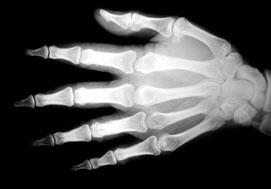

Des études sur l'animal indiquent que l'extrait de Boswellia serrata possède des propriétés anti-inflammatoires. Des études suggèrent qu'il pourrait apporter des effets bénéfiques dans le traitement de l'arthrite ou de la polyarthrite rhumatoïde.

Selon une revue d'études non publiées, des essais préliminaires en double aveugle ont constaté que l'extrait de Boswellia soulageait efficacement les symptômes de la polyarthrite rhumatoïde1. Deux études contrôlées contre placebo, impliquant au total 81 personnes avec une polyarthrite rhumatoïde, ont rapporté une réduction significative de l'enflure et de la douleur après un traitement de trois mois. De plus, une étude comparative portant sur 60 personnes pendant 6 mois a constaté que l'extrait de Boswellia serrata produisait des effets bénéfiques sur les symptômes par rapport à un traitement standard.

Dans une étude randomisée, en double aveugle, contrôlée contre placebo, des chercheurs ont donné un extrait de Boswellia serrata à trente patients souffrant d'une arthrite du genou. Les auteurs de l'étude ont utilisé un modèle croisé.

En d'autres termes, 15 patients ont reçu l'extrait de Boswellia serrata pendant huit semaines tandis que les 15 autres recevaient un placebo. À la fin de ces deux semaines, traitements et sujets ont été inversés.

Tous les patients ayant reçu l'extrait de Boswellia serrata ont rapporté une diminution de la douleur du genou, une augmentation de la capacité à plier le genou et une augmentation de la distance de marche. L'enflure de l'articulation du genou était également diminuée. L'amélioration était statistiquement significative. À l'issue de cette étude, les chercheurs ont recommandé d'utiliser l'extrait de Boswellia serrata, dans le traitement de l'arthrite du genou et ont suggéré qu'il pourrait être également efficace dans le traitement d'autres arthrites2.